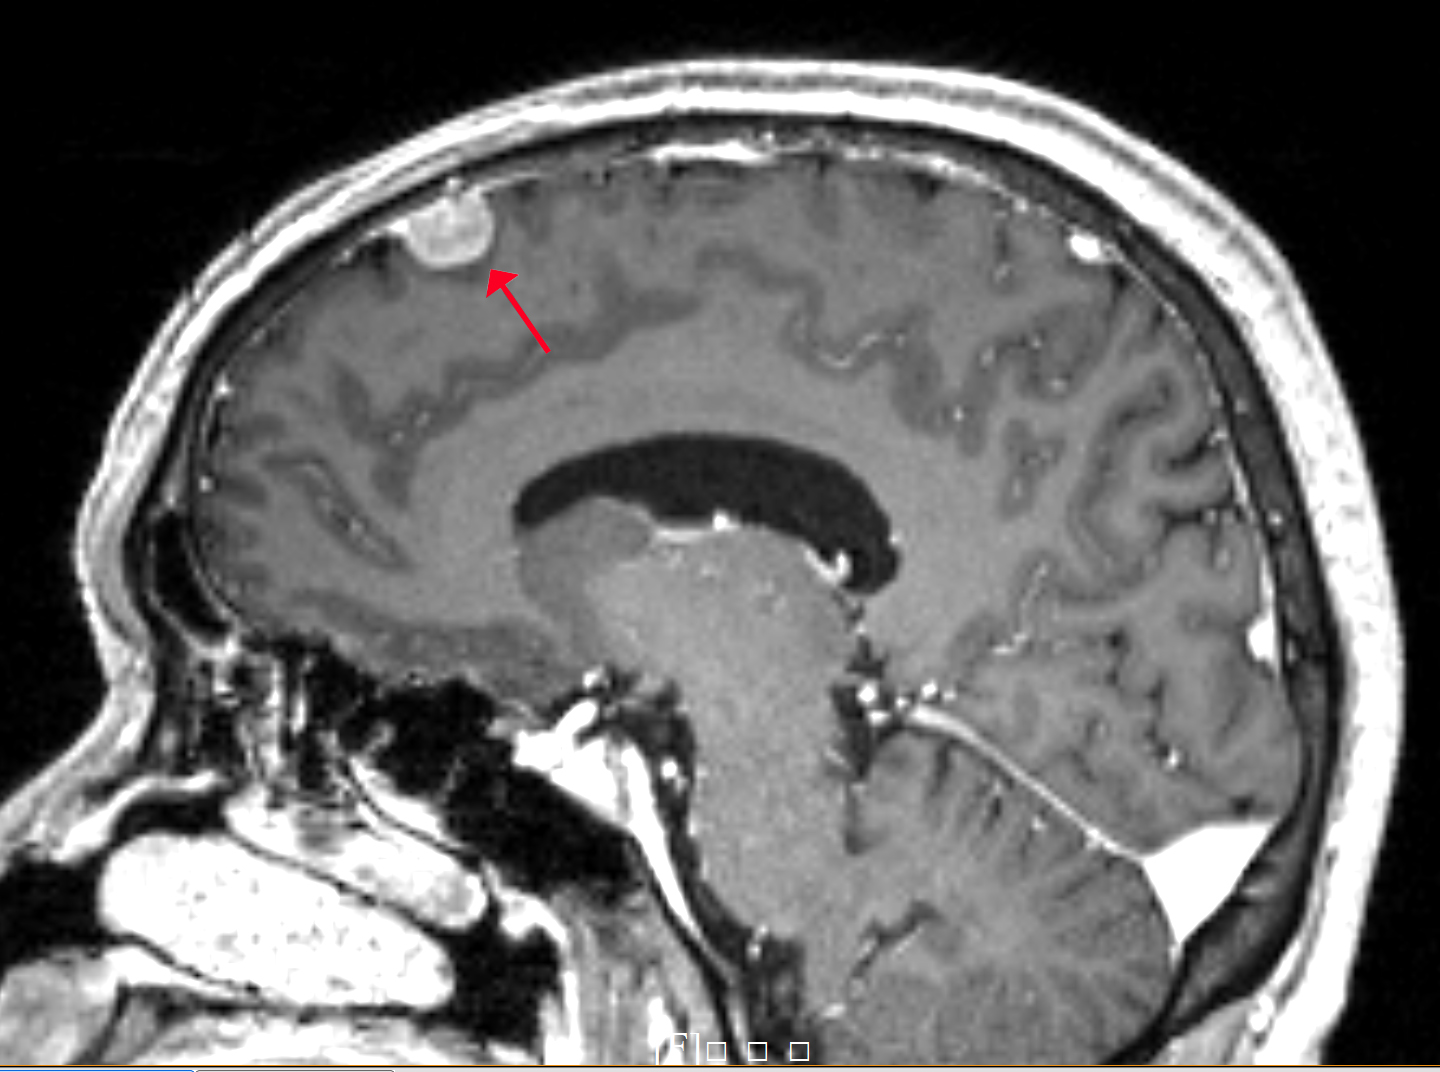

中心病例1:年過(guò)六旬的李老伯來(lái)我中心進(jìn)行體檢,在進(jìn)行顱腦磁共振平掃發(fā)現(xiàn)顱腦右側(cè)額部見(jiàn)一枚占位性病變,建議進(jìn)一步做增強(qiáng)磁共振掃描,證實(shí)為腦膜瘤。(影像圖片見(jiàn)上)